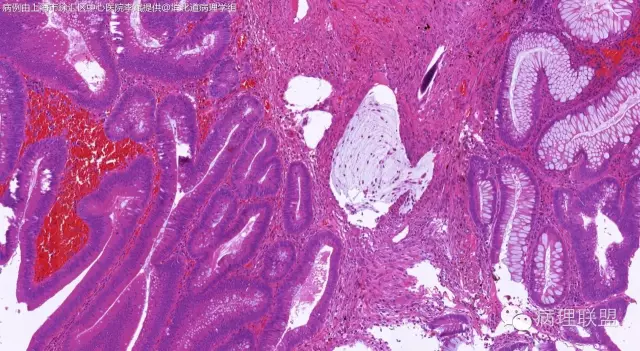

男,64岁,距肛门口45cm息肉大体:灰白结节2*2*1cm(病例由上海市徐汇区中心医院 李斌 提供,致谢!)

管状~绒毛状腺瘤伴低级别上皮内瘤变,黏膜下层部分腺体破裂黏液外溢伴黏液糊形成。

本例部分腺体异位到黏膜下层。

@李斌 李大夫的片子一向漂亮,有赏心悦目的感觉,必须赞一个。这例同意周大夫的意见,低级别绒毛管状腺瘤伴腺体破裂导致的黏液外溢。粘液池周围可见血管扩张淤血、含铁血黄素沉积、肉芽组织形成,提示发生过蒂扭转和出血,这常是造成假浸润、粘液溢出的原因。比较大的绒毛管状腺瘤会有分叶结构,会有比较粗大的平滑肌干,但缺少P-J息肉叶脉样从主干再分支出来的细平滑肌束。作为错构瘤性息肉的一种,P-J息肉的腺体可以分支、扩张、腺腔不规则,但没有细胞异型性,伴发异型增生时,局部出现细胞异型性但不会像这例这样齐刷刷都是异型的腺体。